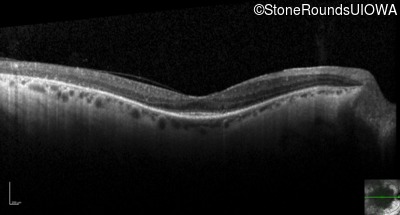

Visit at age: 51 years

Optical Coherence Tomography - Right - 20/50

Exemplar / OCT Stack

OCT Stack